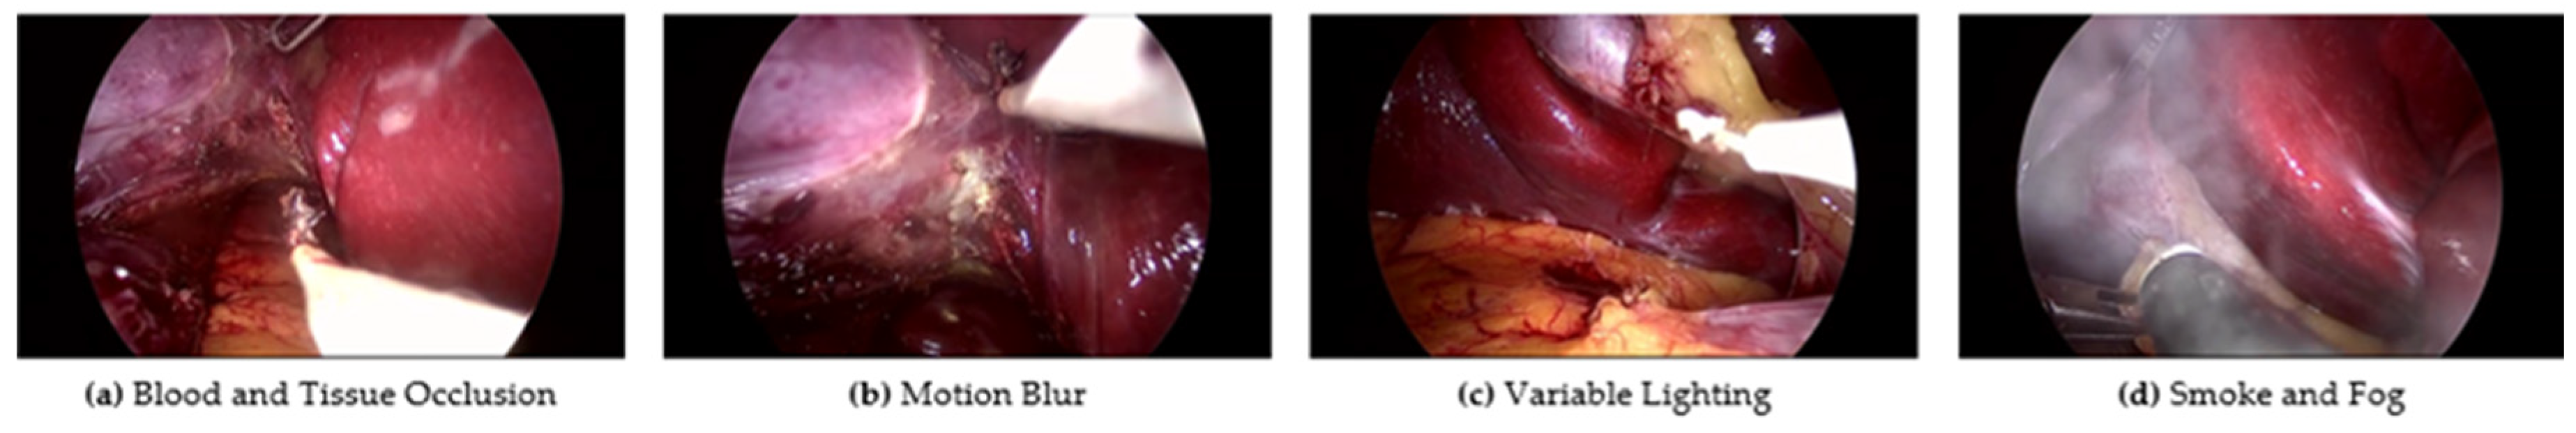

The emerging field of Surgical Data Science (SDS) leverages big data analysis to model surgical processes and develop CASs, representing a significant leap forward in the advancement of surgical procedures [6]. The automatic identification of surgical tools is a crucial component for modelling the surgical processes. Thus, the recognition of surgical tools is addressed in this work. However, Minimally Invasive Surgery (MIS) presents unique challenges, particularly due to the narrow operative space and limited field of view [7,8]. These constraints make precise navigation of surgical tools critical. Moreover, this problem involves other challenging aspects such as rapid camera movements, variable tissues, and obstructive elements like smoke and blood, as illustrated in Figure 1. These challenges hinder the performance of existing methodologies. Combining spatial and temporal features can overcome the limitations of previous approaches and provide more accurate and robust tool classification in MIS environments.

Figure 1. Examples of challenges in surgical tool detection: (a) blood and tissue occlusion, (b) motion blur, (c) variable lighting, (d) smoke and fog obstruction.